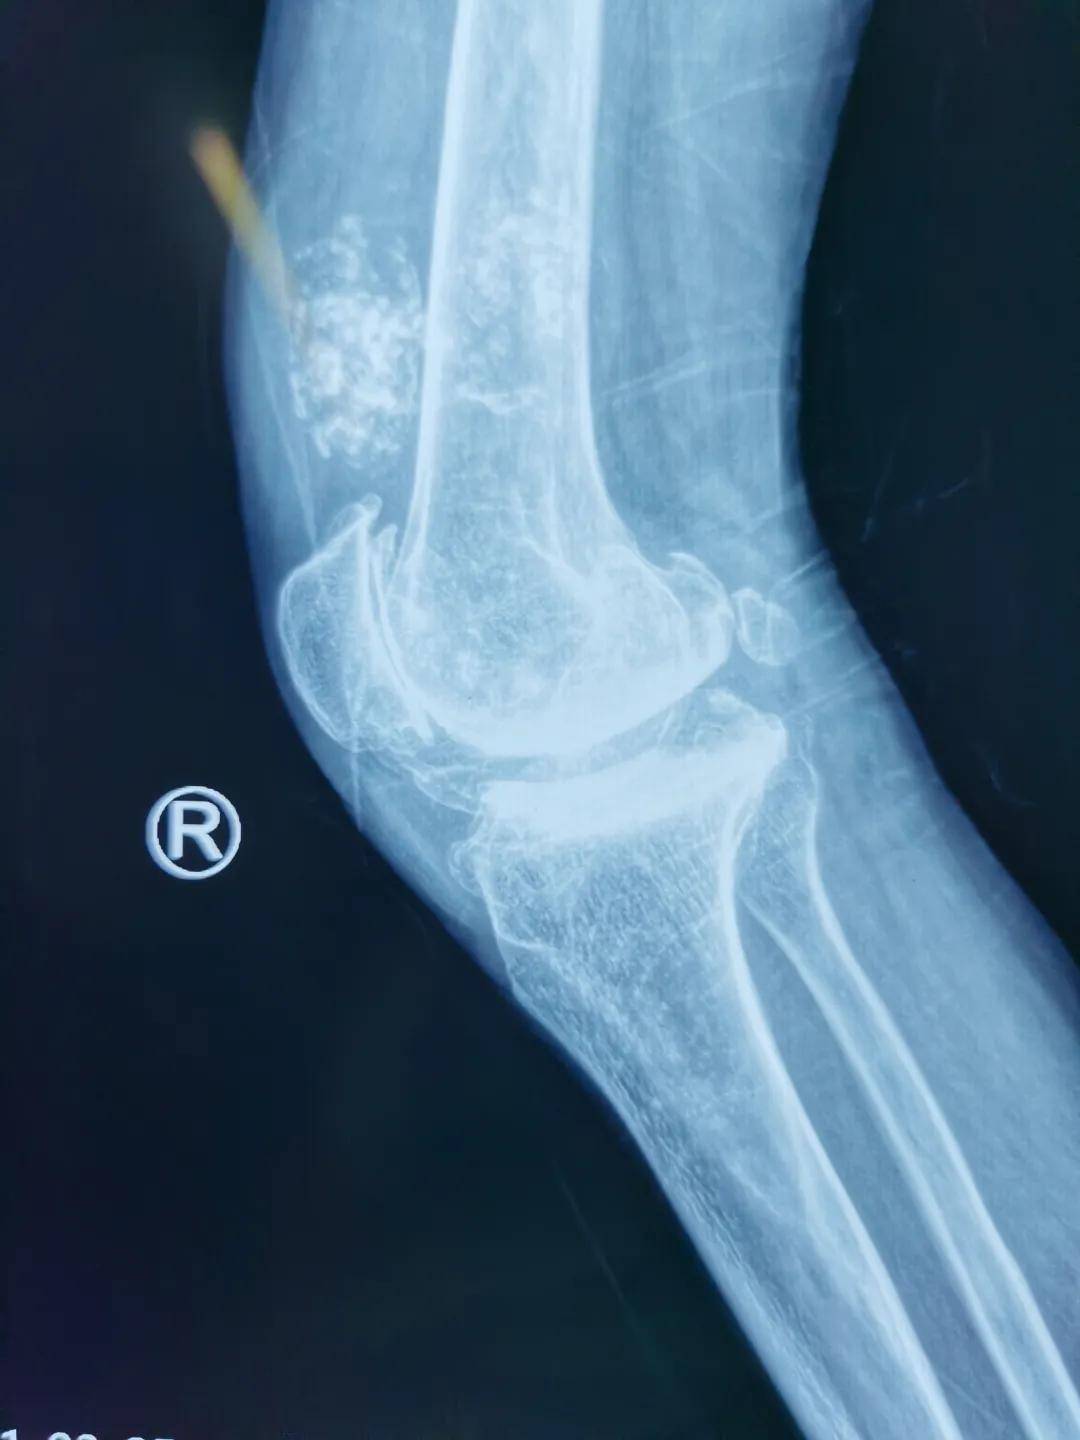

完善各项相关检查后 , 在郭浩院长带领下 , 邀请麻醉科、器械厂家、护士进行学科讨论 , 制定了精细的手术方案 , 由于患者双膝外翻畸形大于30度 , 术前因疼痛完全丧失独立行走能力 , 膝关节外翻畸形的膝关节置换难度大 , 外侧软组织松解困难 , 易出现髌骨脱位 , 神经损伤等并发症 。 在充分完成各项准备后 , 于2021年4月在全麻下行“右侧人工全膝关节置换术” , 术中生命体征平稳 , 手术历时2小时 , 顺利结束 , 患者恢复良好 , 术后第三天便在助步器保护下下地活动 。

此例手术为患者实现了十余年不能站立的行走梦 , 患者看到自己笔直的双腿 , 激动的掉下眼泪 。 西安市红会医院阎良院区在总院的支持与帮助下 , 骨科已经完成了许多例高难度手术 , 优质资源下沉到基层 , 以三级医院的诊疗水平 , 为富阎板块以及周边许多地区患者解决了看病难、就医难问题 , 得到了周边老百姓的信赖与赞扬 。